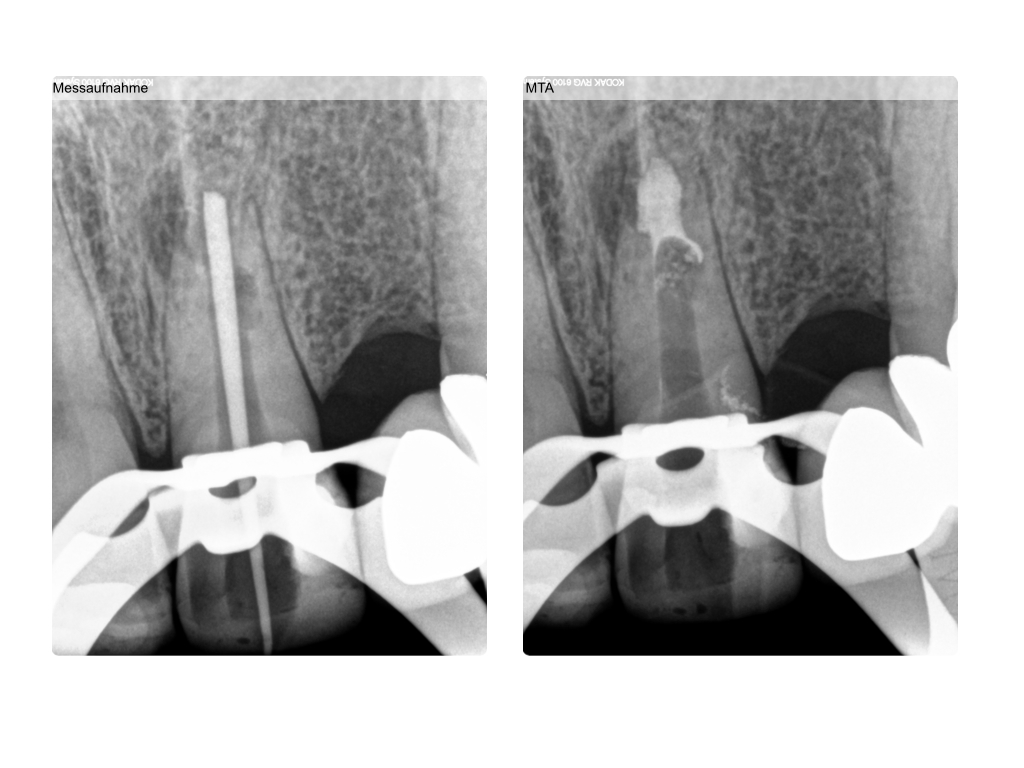

Zahnerhalt mit allen Mitteln?